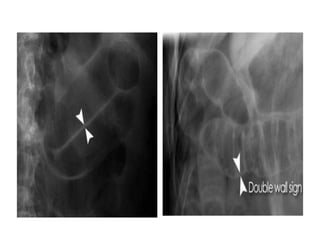

• Rigler's/double wallsign • Rigler's sign (also known as the double wall sign) is the appearance of lucency (gas) on both sides of the bowel wall. Normally only the inner wall of the bowel is visible • If there is pneumoperitoneum both sides of the bowel wall may be visible

• Rigler's/double wall sign

• Rigler's sign (also known

as the double wall sign) is

the appearance of

lucency (gas) on both

sides of the bowel wall.

Normally only the inner

wall of the bowel is visible

• If there is

pneumoperitoneum both

sides of the bowel wall

may be visible